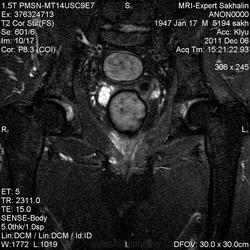

Мужчина 1947 г.рождения.Перенес НМК по ишемическому типу в этом году, в мае  нашла очаг во 2 сегменте правого легкого.Сейчас госпитализирован в неврологическое отделение  для реабилитации.Жалобы на сильную боль в левом тазобедренном суставе.Выполнила рентгенографию сустава, пояснично-крестцового отдела позвоночника.

На рентгенограмме области таза глаз зацепился за большой вертел  слева.Лечащий врач принял решение направить на МРТ.Теперь вообще ничего не понимаю!

Это понятно, что НМК свое черное дело сделало-и гипотрофию мышц, и неадекватность некоторую пациента, но все же-что за включение в левой бедренной кости?

Спасибо большое. Картинки очень хорошие. Мне кажется что ни чего страшного в головках нет. Есть , на мой не слишком опытный глаз, очаги  реконверсии, артрозик. Но если глаз "зацепился" , то можно рекомендовать контрольное исследование в динамике.

Ну и где тут артрозик, господа хорошие? Рентгеновская суставная щель – дай бог всякому и остеофитов нет. А с гипотрофией согласен. Насчёт мышц не скажу, но гипотрофия бедренной кости несомненна. Да только можно ли связать с инсультом… когда он случился?

Вот и я  про то  же!Рентгенологически ( да и МРТ-логически!) суставные щели достаточно приличные.Склероз замыкательных пластинок-да, мелкие узуративные дефекты -наскребла немного для дегенеративных проявлений .Инсульт был 4-5 месяцев назад.